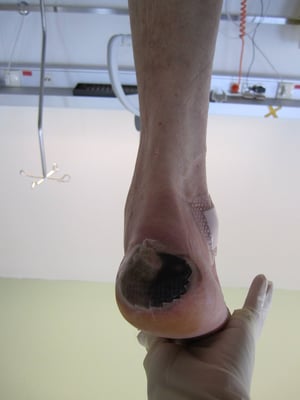

Ein Diabetiker mit Polyneuropathie und/oder Durchblutungsstörung hat einen Risikofuß und benötigt einen Spezialschuh für Diabetiker mit entsprechender Fußbettung. Hat ein solcher Risikopatient zusätzlich starke Fußveränderungen oder offene Wunden (Ulcus), so ist ein orthopädischer Maßschuh unerlässlich.

Dieser Entlastungsschuh wird je nach Bedarf mit Rolle und Hohllegungen (Tieflegung) zur Druckumverteilung bzw Druckentlastung angefertigt. Für unsere Entlastungsschuhe verwenden wir nur besonders hygienisches und sogar waschbares Material. Durch die individuelle Anpassung an die jeweiligen Bedürfnisse unserer Kunden kann die bestmögliche Versorgung gewährleistet werden. Unsere Entlastungsschuhe sind federleicht, verfügen über eine stabile Sohle und eine gute Rolle.

Entlastungsorthese

Dieses orthopädie-technische Hilfsmittel dient zur Totalentlastung des orthopädischen Fußes. Abhängig vom Alter und von Begleiterscheinungen des Patienten werden Verletzungen, Geschwüre und Deformitäten weitgehend vermieden und die Mobilität verbessert. Weiters kann man durch den Schutz einer Orthese die Wundheilung und somit die Gefahr einer Amputation oder Infektion vermeiden. Alles in allem gesehen führt die Verwendung einer Orthese zur Steigerung der Lebensqualität von Diabetespatienten. Dieser Stützapparat ist jederzeit abnehmbar, wodurch eine regelmäßige Fußpflege möglich ist.